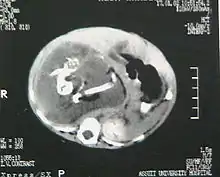

Fetus in fetu (or foetus in foetu) is a rare developmental abnormality in which a mass of tissue resembling a fetus forms inside the body of its twin. An early example of the phenomenon was described in 1808 by George William Young.[1]

There are two hypotheses for the origin of a "fetus in fetu". One hypothesis is that the mass begins as a normal fetus but becomes enveloped inside its twin.[2] The other hypothesis is that the mass is a highly developed teratoma. "Fetus in fetu" is estimated to occur in 1 in 500,000 live births.[3]

Fetus in fetu may be a parasitic twin fetus growing within its host twin. Very early in a monozygotic twin pregnancy, in which both fetuses share a common placenta, one fetus wraps around and envelops the other. The enveloped twin becomes a parasite, in that its survival depends on the survival of the host twin, by drawing on the host twin's blood supply. The parasitic twin is anencephalic (without a brain) and lacks some internal organs, and as such is unable to survive on its own. As the host twin has to "feed" the enveloped twin from the nutrients received over a single umbilical cord, they usually die before birth.